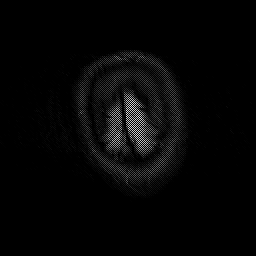

Subacute Stroke, overlay -- Slice #25

[Home][Help][Clinical] Slice 25